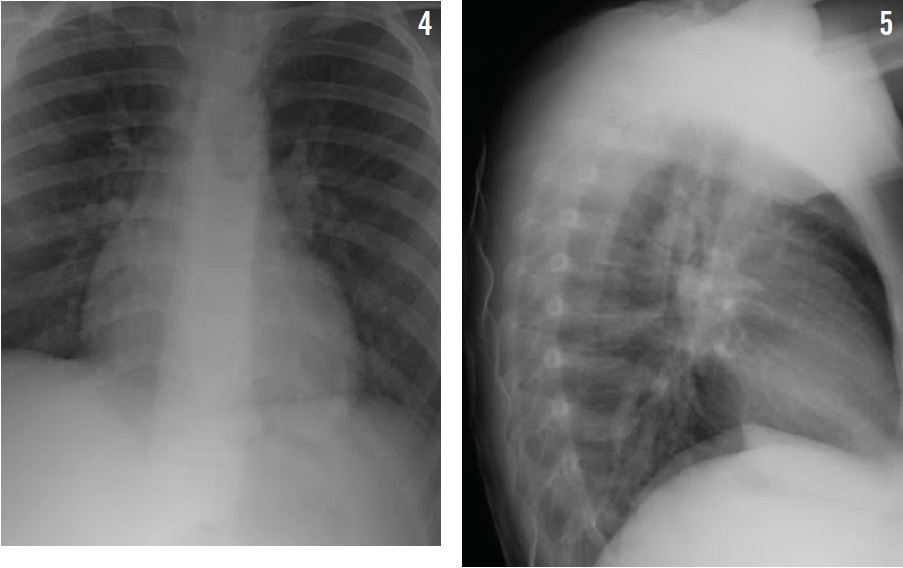

Chest radiography showed patchy areas of consolidation distributed in both lungs, suggesting bronchopneumonia (Figures 4 and 5). Laboratory tests showed: hemoglobin 14 g/dL; total leukocyte count (TLC) 8,300/mm3; neutrophils 85%; and lymphocytes 9%. Testing results for infectious mononucleosis were negative. Results for the patient’s complete metabolic panel were normal. A blood culture showed no growth, and his respiratory viral panel was negative.